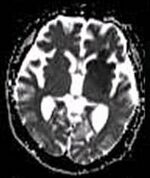

DWI showing cortical ribbon-like high signal consistent with diffusion restriction in a patient with known MELAS syndrome